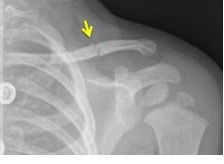

Het sleutelbeen is het bot tussen uw schouder en uw borstbeen. Een gebroken sleutelbeen heet ook een claviculafractuur. De behandeling is het dragen van een sling. Een sling is een soort mitella.

Een gebroken sleutelbeen komt vaak voor bij kinderen. De behandeling bestaat uit het dragen van een sling. Bij kleine kinderen lukt het vaak niet om hen een sling te laten dragen. Dit is niet erg. Een gebroken sleutelbeen herstelt bijna altijd volledig.